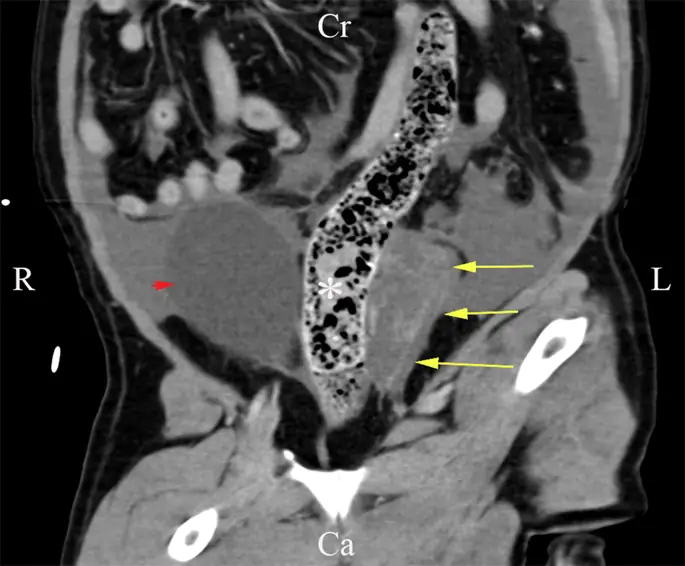

Выполнена контрастно-контрастная томография торакоабдоминальной компьютерной томографии (КТ). В грудной полости мягкий ателектаз клинического значения не обнаружен, в то время как в брюшной полости обнаружен большой объем эхогенной перитонеальной жидкости без контрастного усиления (рис. 1). На левой стороне мочевого пузыря, внутри очагов асцита, была обнаружена фокальная область усиливающего контраст полосатого материала, прилегающая к нисходящей ободочной кишке, левой бедренной артерии, культи матки и левой стороне мочевого пузыря (рис. 2). Единственный маленький (2.5 мм в диаметре) узелок, ослабляющий мягкие ткани, был обнаружен рядом с селезенкой, дорсально с левой стороны живота. Кистозная структура не была снова удалена, и узелок селезенки был слишком мал, чтобы аспирировать. После этих результатов нашими дифференциальными диагнозами были неоплазия, фибриновый материал или гранулематозное воспаление. В качестве диагностической и терапевтической меры была выполнена вентральная срединная исследовательская лапаротомия от мечевидного отростка до лобка. Большая, тонкостенная, заполненная жидкостью структура была обнаружена в левой части брюшной полости, простираясь от левого забрюшинного пространства, которая расширила дорсальную брюшную брюшину и заставила ее отклониться, чтобы лежать дорсально по отношению к мочевому пузырю. С левой стороны жидкость расширялась в левой боковой связке мочевого пузыря и окружала левый мочеточник (рис. 3). Ножка матки не была вовлечена. Кистозная структура была дренирована, чтобы отличить патологическую стенку кисты от нормальных анатомических структур. Оба мочеточника были обнажены, поэтому они не прилипали к кистозной структуре или дорсальной брюшине. Большая часть стенки кисты (около 90%) была удалена при сохранении почек, мочеточников, мочевого пузыря и внутренней и наружной подвздошной артерии и вены. Никаких дополнительных кистозных образований в забрюшинном пространстве не выявлено, а также не было признаков метастазирования в брюшные лимфатические узлы или органы. Узелок селезенки, видимый при УЗИ брюшной полости, не может быть визуализирован макроскопически. Забрюшинное пространство было сальниковой, чтобы помочь в продолжающемся дренировании. Иссекаемая ткань была представлена на гистологическое исследование. Собака выздоровела незаметно и через 2 дня выписана после операции.

фигура 2

Спинной отдел брюшной полости на КТ, без контраста. Забрюшинная кистозная структура (стрелка) прилегает к толстой кишке (звездочка). Мочевой пузырь (наконечник стрелы) можно визуализировать с правой стороны ободочной кишки. R справа, L слева, Cr черепной, Ca каудальный